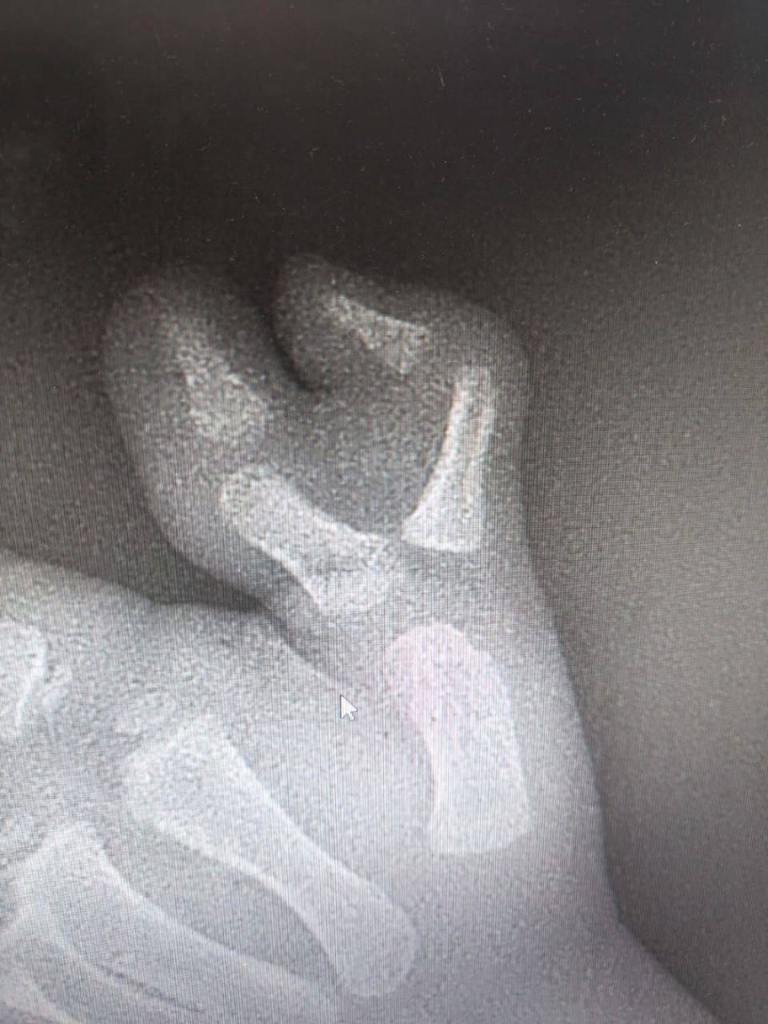

В Московскую областную детскую клиническую травматолого-ортопедическую больницу (МОДКТОБ) в плановом порядке поступил трехлетний мальчик с врожденной аномалией развития кисти.

У маленького пациента рос добавочный палец, вызывая как физические, так и психологические трудности. После всех необходимых диагностических мероприятий ребенку провели операцию.

— Мы понимаем, насколько это важно для детей иметь возможность полноценно развиваться и заниматься различными активностями. Ребенку проведена реконструктивная операция и удален добавочный палец. Благодаря хирургическому вмешательству, мальчику не только создано анатомически верное строение сустава первого пальца кисти, но и предупреждено развитие комплексов у пациента в дальнейшем, — прокомментировал заведующий отделением, врач-травматолог-ортопед МОДКТОБ Виталий Куваев.

Операция прошла успешно. Сейчас ребенок уже выписан из стационара на амбулаторное лечение по месту жительства. После полного восстановления мальчика ждет повторная операция для удаления металлоконструкции. В дальнейшем функция кисти полностью восстановится.